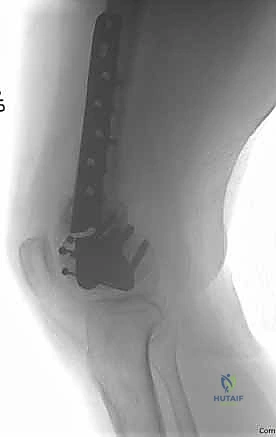

### FIG 9 • Critically ill elderly polytrauma Jehovah's witness patient with left C1 distal femur fracture. A,B. Initial injury AP and lateral views. C,D. Due to extremely low hematocrit, external fixation was the only surgical option allowed to minimize blood loss. Radiographs in bridging external fixation. The AP shows excellent alignment but the lateral shows the expected extension deformity secondary to pull of gastrocsoleus complex. E,F. After 5 weeks in an external fixator, AP and lateral radiographs show callus formation (red arrows). Patient is now cleared for definitive surgical intervention. Antegrade intramedullary nailing has been described and can be used for distal fractures with a large enough distal segment to allow for two locking screws. Malalignment has been a problem, as has adequate fixation. 4, 8 Retrograde intramedullary nailing can be used in the following cases ( FIG 10): All extra-articular type A fractures greater than 4 cm from the joint. This minimal length of the distal femur allows for multiplanar interlocking in the distal fragment. Type C1 or C2 fractures where the articular fracture can be anatomically reduced closed or with limited exposure. Percutaneous screws are used for the articular injury. Periprosthetic fractures around a total knee arthroplasty with an “open box” femoral component Most surgeons prefer to use a long nail, but short supracondylar nails are available as well. Multiple-hole short supracondylar nails have fallen out of favor. Plate fixation ORIF with plates can be used for all types A and C fractures but is ideal for the following injuries: Very distal type A fractures within 4 cm of the knee joint All articular type C fractures, but always for C3 types Periprosthetic fractures about a “closed box” femoral component of a total knee arthroplasty The partial articular type B1 or B2 if an antiglide plate is needed Plate options (preferred to least preferred; fixed-angle devices preferred) Fixed-angle locking plates (percutaneous jigs are advantageous and allow for minimally invasive techniques) Variable-angle (polyaxial) locking plates—allow for “fixed variable locking” within a defined range. It is useful for distal fractures and allows for increased screw 473 trajectories to gain additional locked fixation in short segments, which may not be feasible with fixed-angle trajectory plates ( FIG 11).

### FIG 10 • A,B. AP and lateral radiographs of an elderly patient with multiple comorbidities with an extra-articular distal femur fracture (AO type A; an incomplete intercondylar split— red dashed arrow). C,D. Postoperative radiographs showing stabilization with retrograde intramedullary nail. E,F. One-year postoperative radiographs showing a healed fracture with some subsidence of the metaphyseal region and mild protrusion of hardware through the notch. Ninety-five-degree condylar screw Ninety-five-degree blade plate Nonlocking plates with or without medial support (medial plate or external fixation) Limited internal fixation Limited fixation with screws only can be used for partial articular type B, especially type B3. The amount of open reduction required depends on the adequacy of closed reduction techniques and obtaining an anatomic reduction of the joint surface. Headless screws are useful for type B3 fractures in which the screws have to penetrate the joint surface ( FIG 12). Countersinking the screw heads can also be performed. Biomechanics of fixation: implant considerations There has been concern that the newer locking plate constructs are too stiff, resulting in inconsistent and asymmetric callus formation. 9 Some clinical evidence show less callus formation with stainless steel plates versus titanium plates. 9 Conversely, a biomechanical study has not shown a significant difference mechanically between constructs of stainless steel LISS plates with bicortical screws or titanium LISS plate with unicortical screws.1 474